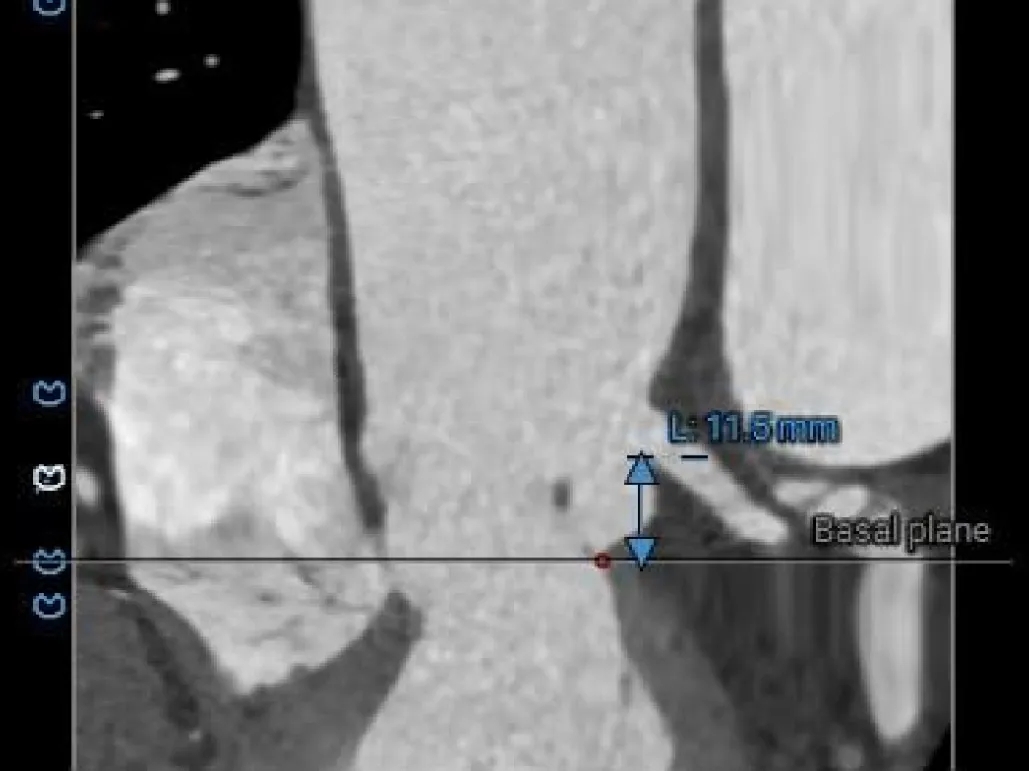

冠脉风险评估

LCA Height

RCA Height

LCA & Leaflet

RCA & Leaflet